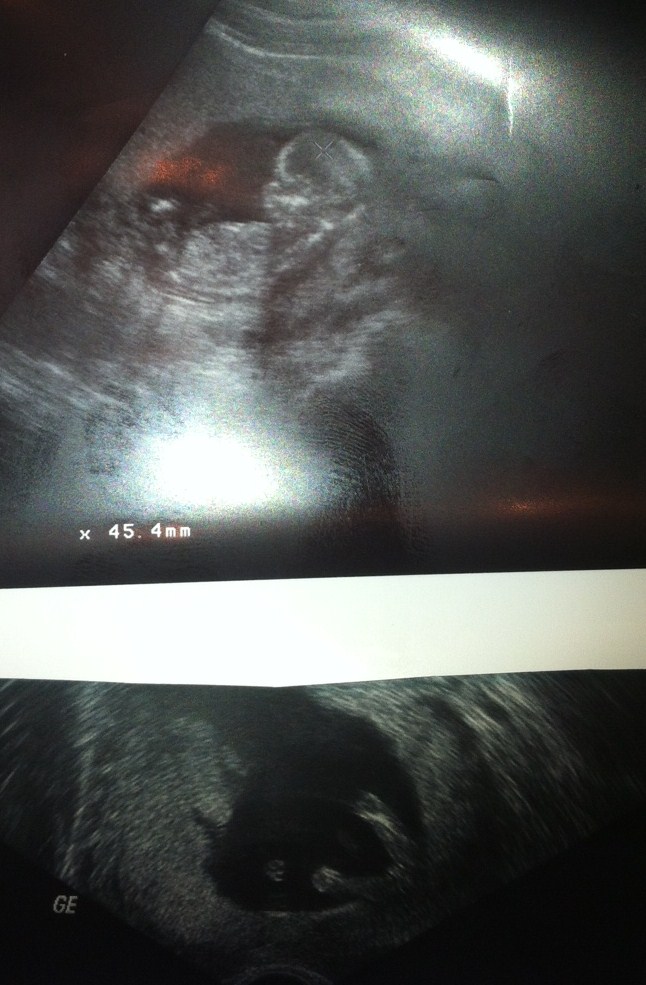

Can you pleas tell me if that is a girl ore a boy ? -- And why...

I have bleedings so I have a few pics from differnt doctors .

Ferdinand - Ultrasound

Ferdinand - Gender :-)

:ttcgirl: ore :DS: ?